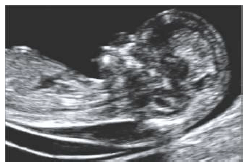

Sobre a imagem abaixo, podemos concluir que há, EXCETO: